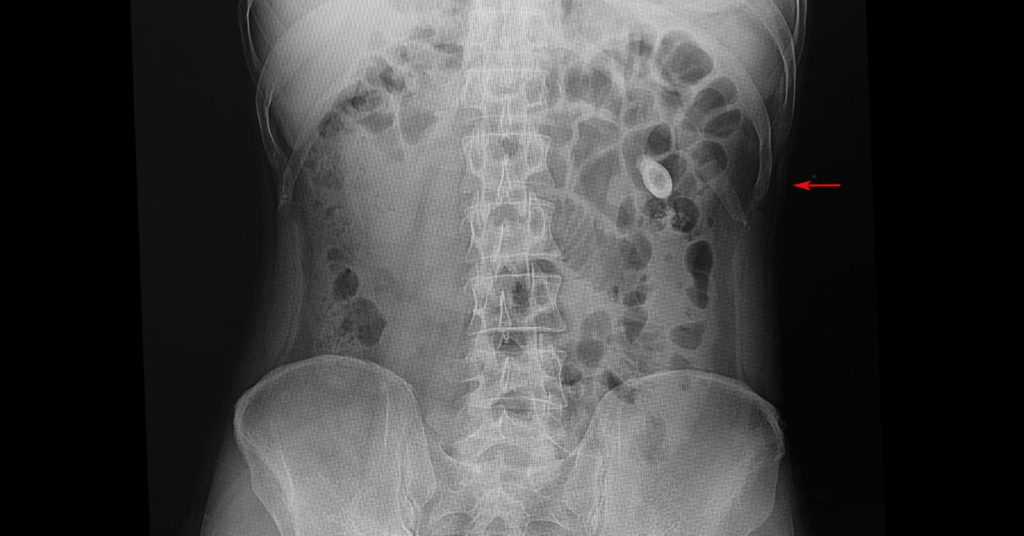

Symptoms of Kidney Stones January 31, 2021 by Ali Mustafa Symptoms of Kidney Stones About Ali Mustafa Previous Post:Symptoms of Kidney Stones